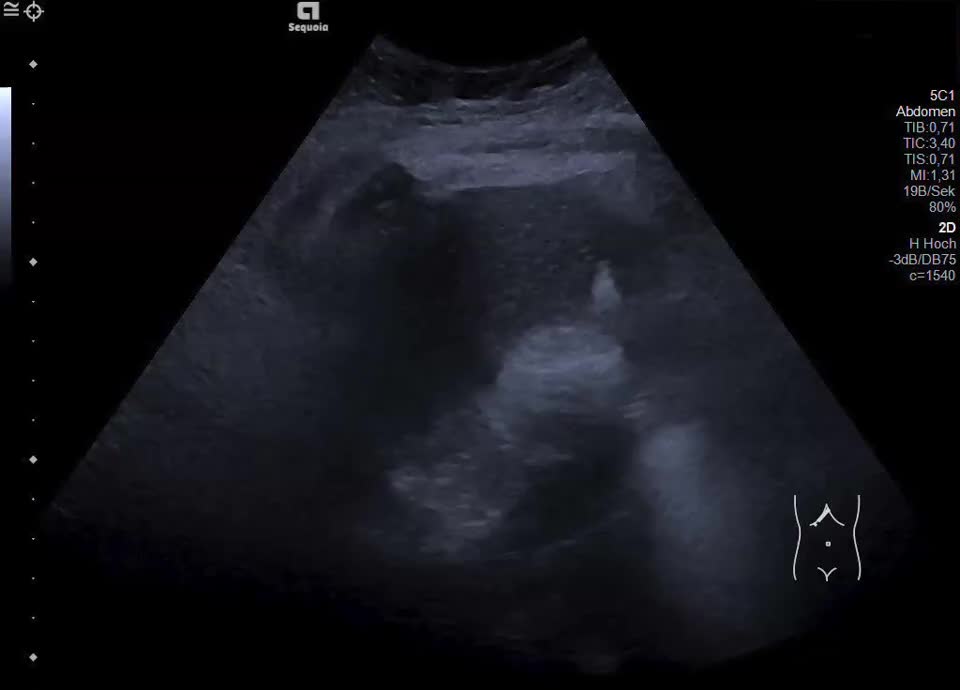

Normal Gallbladder

• Gallbladder in transversal view